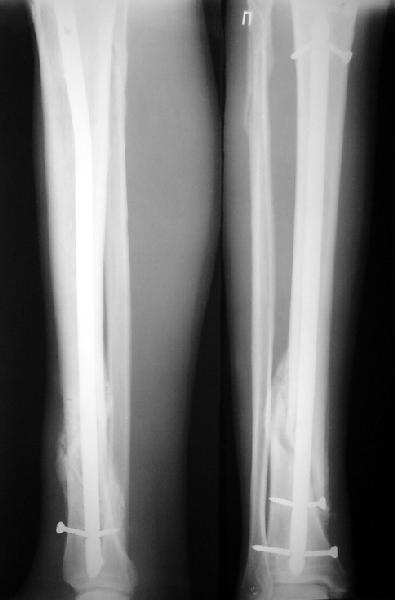

Как мне показать пример? Фото стоящего на одной оперированной конечности пациента? O! Пример, подвигнувший нас на некоторое изменение технологий. Пациент этот ходил с полной нагрузкой вопреки рекомендациям. В качестве подтверждения - сломанный проксимальный статический винт к 1 мес., а к 2 мес. - все остальные. Сейчас мы перешли на более fool-proof остесинтез.

На мой взгляд, на снимках, приведённых Вами - неправильно сростающийся перелом дистальной трети большеберцовой кости, состояние после остеосинтеза интрамедуллярным гвоздём.

Как Вы пишите снимок под номером 1 - менсяц после операции, под номером 2- два месяца после операции.

I think that the X-Rays show S/P IMN of Spiral # of the Distal Tibia consoles in misalignment.

You wrote that a picture number 1 - f month after the surgery, and number 2-two months after the surgery.

Ok. А также и следующий, в 3 месяца.